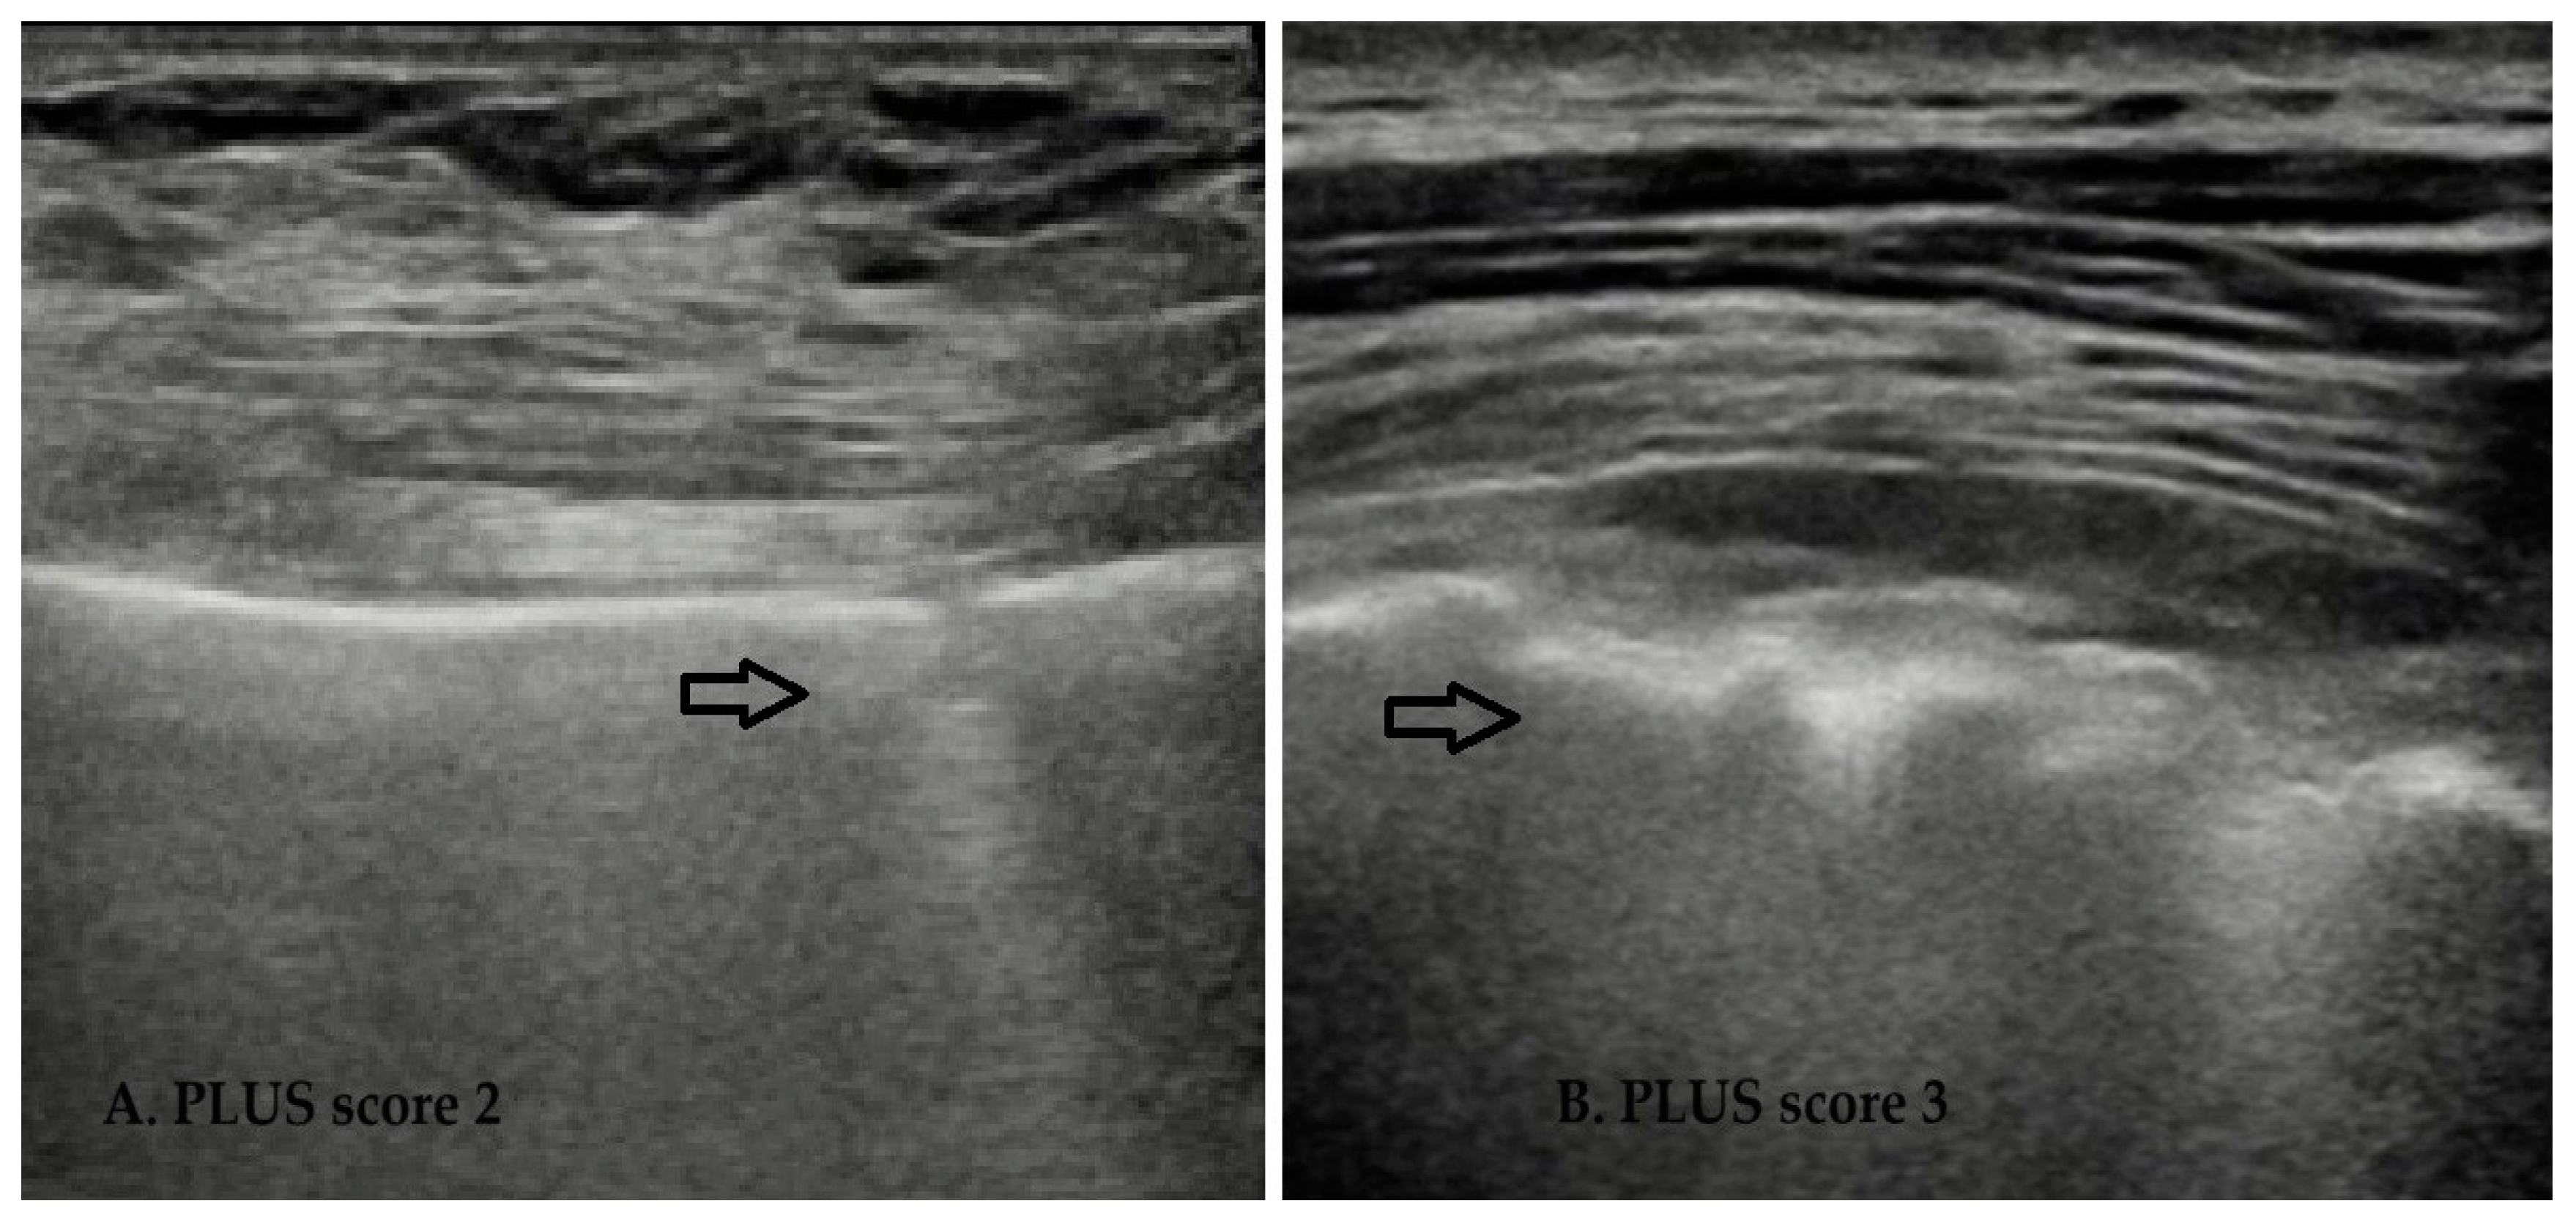

- PLUS 2, disrupted pleural line (“fragmented”);

- PLUS 3, subpleural consolidation (subpleural echo-poor region or “tissue-like”);